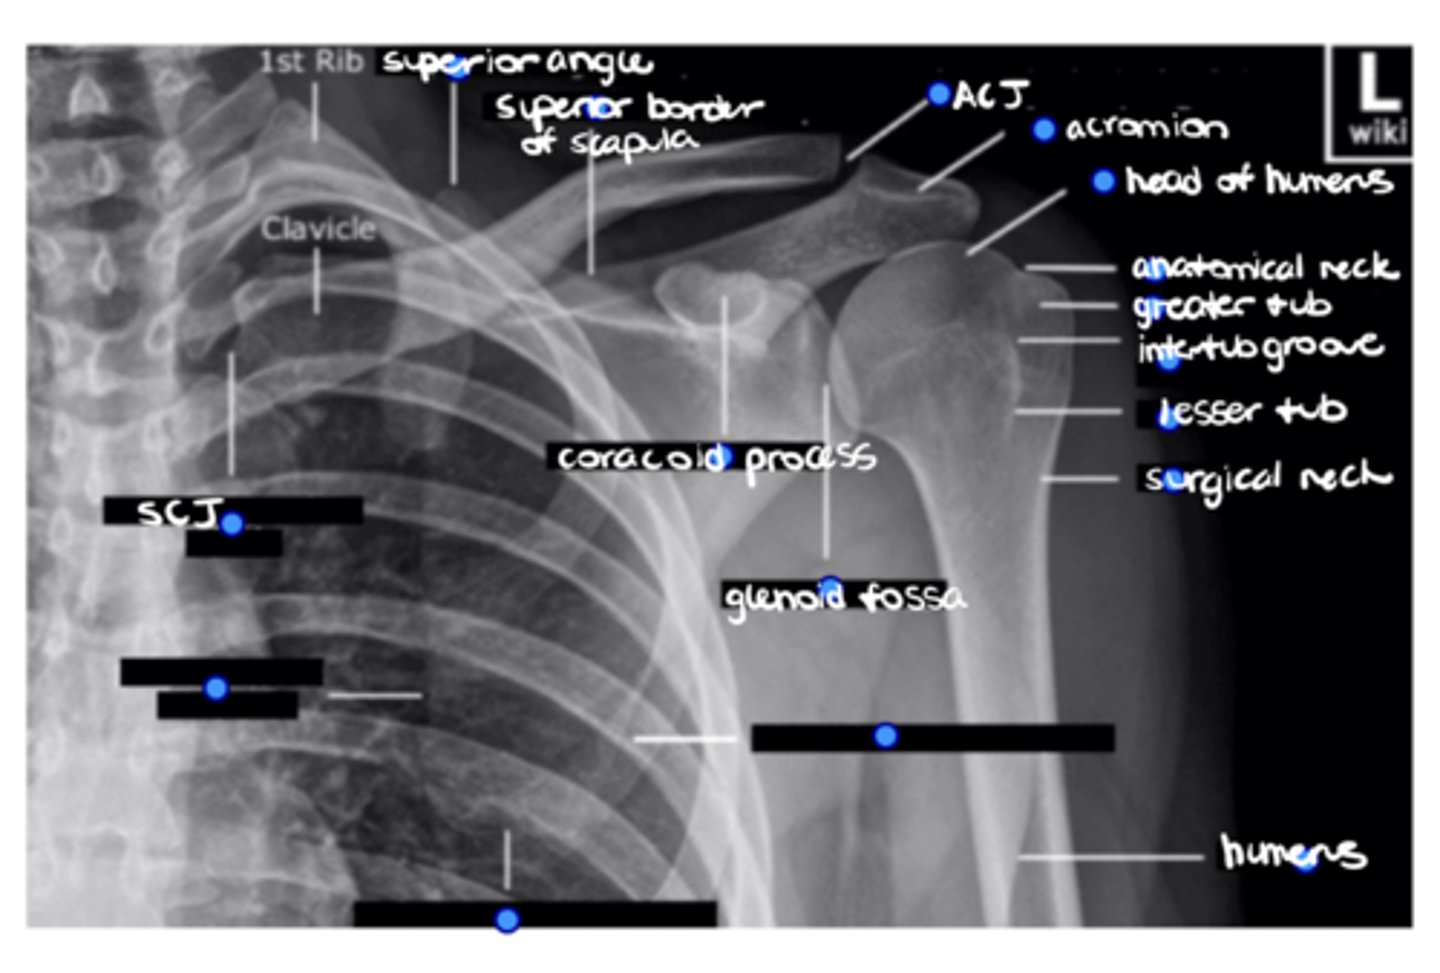

1. Lateral border of the scapula

2. Inferior angle of the scapula

3. Medial border of the scapula

ID the 3 missing structures.

SCJ

ID the missing structure.